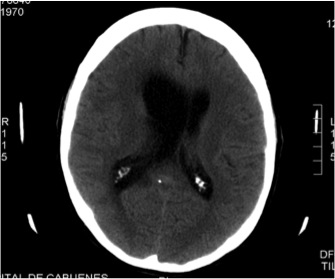

Lymphomatoid Granulomatosis of Central Nervous System and Lung Driven by Epstein Barr Virus Proliferation: Successful Treatment with Rituximab